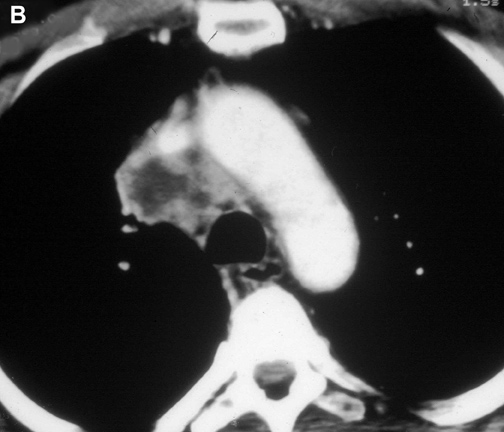

Figure 2A Figure 2B Figure 3

Figure 2A & B. (A) Lung cancer invading the superior vena cava. (B) Mediastinal lymph nodes invading the superior vena cava. Figure 3. Cortical thymoma invading the superior vena cava.